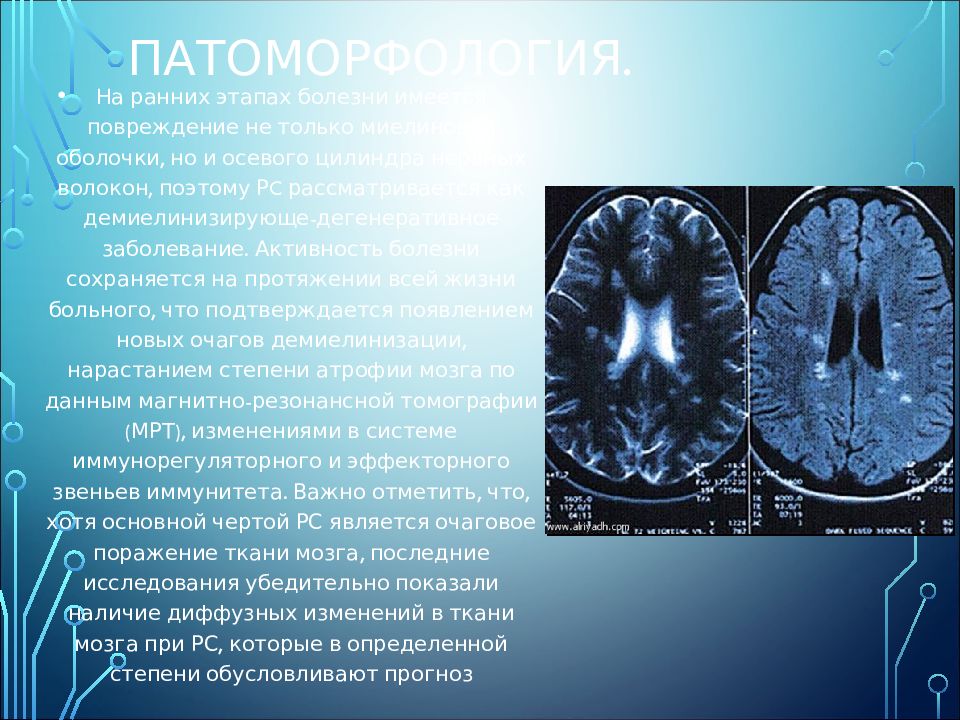

Информация о диссеминированном рассеянном энцефаломиелите